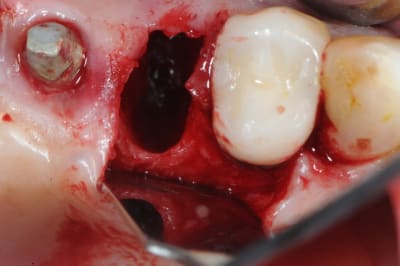

1- curette en appuie sur la face vestibulaire montrant la destruction osseuse.

2- lambeau pleine épaisseur en palatin pour aller chercher un bout de conjonctif qui soit pédiculé.

3 je décole à partit des rebords de la déhiscence osseuse et reste en contacte permanent avec la corticale osseuse tout en décollant la gencive (elle est soulevé donc)

4- comblement avec de la poudre de perlin-pin-pin

( désolé je suis pas au cabinet et je sais plus ce que j'ai mis dedans)

5-6- sutures du conjonctif pour obtenir l'étanchéité (enfin , on essaye)